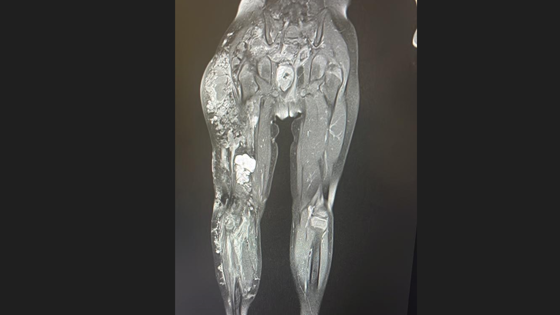

В Кузбассе ребенку удалось поставить диагноз, который зафиксирован примерно у тысячи людей во всем мире. Это сосудистая дисплазия Клиппеля-Треноне-Вебера.

Чтобы выявить эту врожденную болезнь, потребовалось провести сложнейшее исследование с помощью МРТ-аппарата. Диагностику провели в детской больнице имени Атаманова в Кемерове.

– Сложность была в том, что сосудистая аномалия распространялась из полости малого таза на протяжении всей нижней конечности до стопы, – сообщили представители Миндзрава Кузбасса.